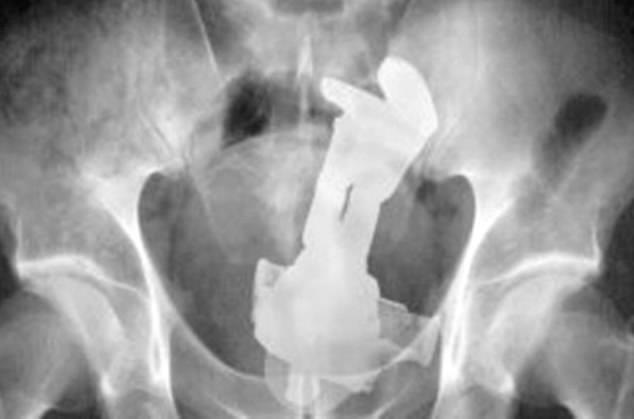

7. Ένα ερωτικό βοήθημα